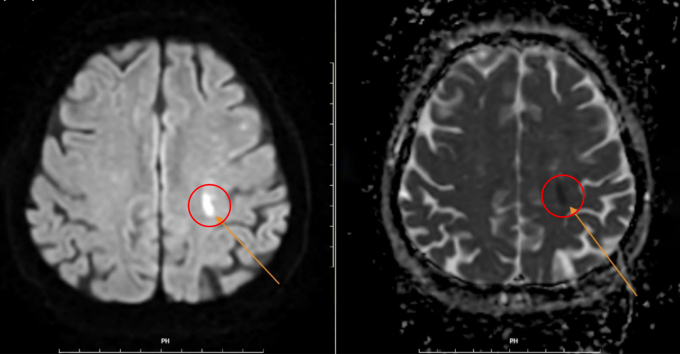

Để tránh bỏ lỡ thời gian điều trị lý tưởng, êkíp kích hoạt quy trình Code stroke (cấp cứu đột quỵ) để chụp CT và MRI cho kết quả sớm nhằm khẳng định chẩn đoán. Kết quả chụp MRI cho thấy nhồi máu, phù hợp với biểu hiện yếu liệt nửa người bên phải (yếu liệt xảy ra bên nào thì vị trí nhồi máu não ở bên ngược lại).

Chưa tới một giờ sau khi tự phục hồi, bà Tiên xuất hiện các triệu chứng trở lại, yếu liệt tay chân nặng hơn. Tuy nhiên, tình trạng đột quỵ xảy ra trong giai đoạn giờ "vàng" (trong 4,5 giờ đầu tiên kể từ khi có triệu chứng), bác sĩ chỉ định người bệnh có thể sử dụng thuốc tiêu sợi huyết đường tĩnh mạch, giúp tan cục máu đông và tái thông mạch máu não.